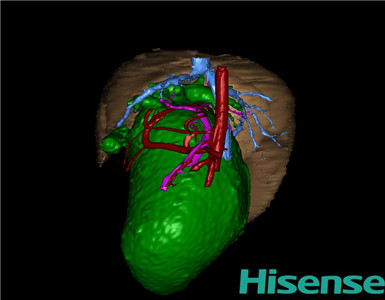

CT结果输入海信CAS系统后行3D重建及手术规划后,于2015-3-5全麻下行“胆总管囊肿切除+胆囊切除+胆总管-空肠吻合术”手术治疗:

将0.625mm双源薄层CT资料的静脉期和动脉期Dicom格式文件导入海信CAS系统。

通过调节窗宽窗位调整CT序号,对肝实质,胆囊,胆总管,下腔静脉,肝动脉、门静脉及肝静脉等进行三维重建;系统自动计算肝脏体积。

术前三维重建:

重建图片